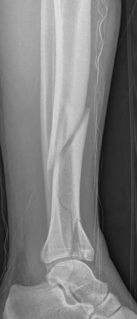

The management of complex tibial shaft fractures with extension into the distal articular surface (the tibial plafond or pilon) represents one of the most formidable challenges in orthopedic traumatology. These injuries typically result from high-energy mechanisms, such as a fall from a significant height or a motor vehicle collision, where axial loading forces are combined with severe rotational and shear vectors. The classic presentation, as highlighted in our index case of a 26-year-old male who fell 3 meters into a hole, involves not only catastrophic bony disruption but also devastating injury to the surrounding soft tissue envelope. The delicate nature of the soft tissues in the distal third of the leg, characterized by sparse muscular coverage and a precarious vascular supply, dictates the entire trajectory of clinical decision-making.

The patho-epidemiology of these injuries is inextricably linked to the incidence of acute compartment syndrome. High-energy axial loads result in rapid swelling, hemorrhage, and edema within the unyielding fascial compartments of the leg. As demonstrated in our reference case, clinical examination often reveals a tense, swollen limb necessitating an immediate four-compartment fasciotomy. The dual-incision technique remains the standard of care to decompress the anterior, lateral, superficial posterior, and deep posterior compartments. The presence of fasciotomy wounds further complicates the surgical approach for definitive internal fixation, requiring strict adherence to the principles of damage control orthopedics (DCO).

Initial management in these high-velocity scenarios mandates the application of a spanning external fixator to achieve skeletal traction, restore length, and allow the soft tissue envelope to recover. This temporary stabilization minimizes ongoing secondary soft tissue trauma from mobile fracture fragments. However, the application of external fixators is not without risk; meticulous pin placement is required. For instance, calcaneal transfixion pins must be placed with strict attention to the neurovascular bundle to avoid iatrogenic tibial nerve irritation, an issue that required revision in the early phase of our index patient's care.